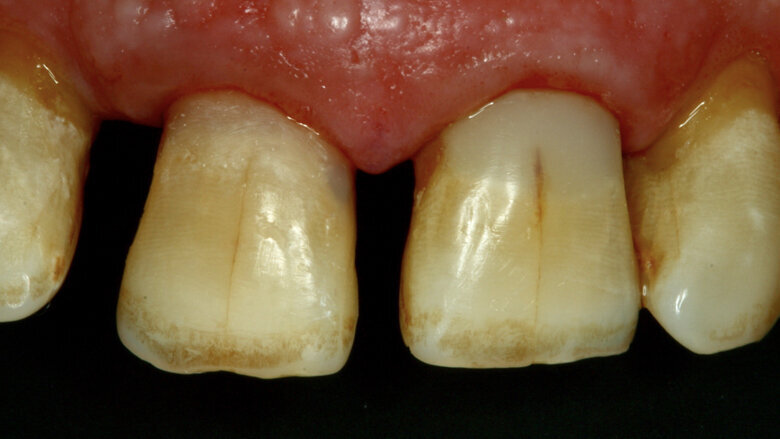

Paciente masculino de 65 años de edad se presenta al consultorio con lesiones de caries cavitadas en dentina activa (ICDAS 5) en dientes 11 y 21 (Figura 1). La lesión de la pieza 21 es extensa, mediante examen radiográfico y pruebas de vitalidad se diagnostica ausencia de compromiso pulpar. Como la lesión se extiende infra-gingivalmente, se opta por colocar dos hilos retractores 000 y 00 (Ultrapack, Ultradent, EE UU) y aislamiento absoluto con hilo dental tipo teflón y un clamp para anteriores (Figuras 2 y 3). Se inicia el procedimiento de remoción químico-mecánica utilizando un agente enzimático (Brix3000, Brix Medical Science, Argentina) durante 2 minutos (Figura 4). Utilizando curetas (Maillefer, EE UU) se elimina la dentina infectada (Figura 5) y el esmalte sin soporte dentinario (Figura 6) es eliminado con una fresa multilaminada (Figura 7) para mejorar el mimetismo y la adhesión al esmalte. Se complementa la instrumentación mecánica en el límite amelo-dentinario (Figuras 8 y 9).

La cavidad es lavada con un micro-cepillo con piedra pómez y clorhexidina 0,12% (Figura 10) para colocar silicato de calcio modificado por resina (Theracal LC, Bisco, EE UU) por la proximidad a la pulpa (Figuras 11 y 12). Se condiciona el esmalte mediante la técnica de grabado selectivo (Figura 13) y se utiliza un adhesivo self-etch de dos pasos (Figuras 14 y 15), se adiciona la resina compuesta (Forma, Ultradent, EE UU) y finalmente se realiza el protocolo de pulido (Figura 16). La restauración finalizada se presenta en la Figura 17 y al remover el aislamiento en la Figura 18.